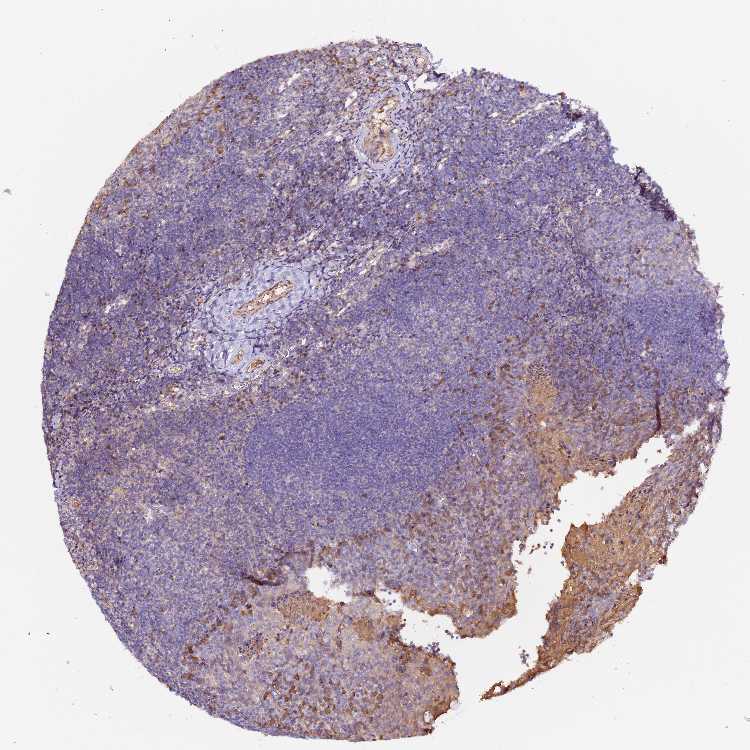

NEDD4